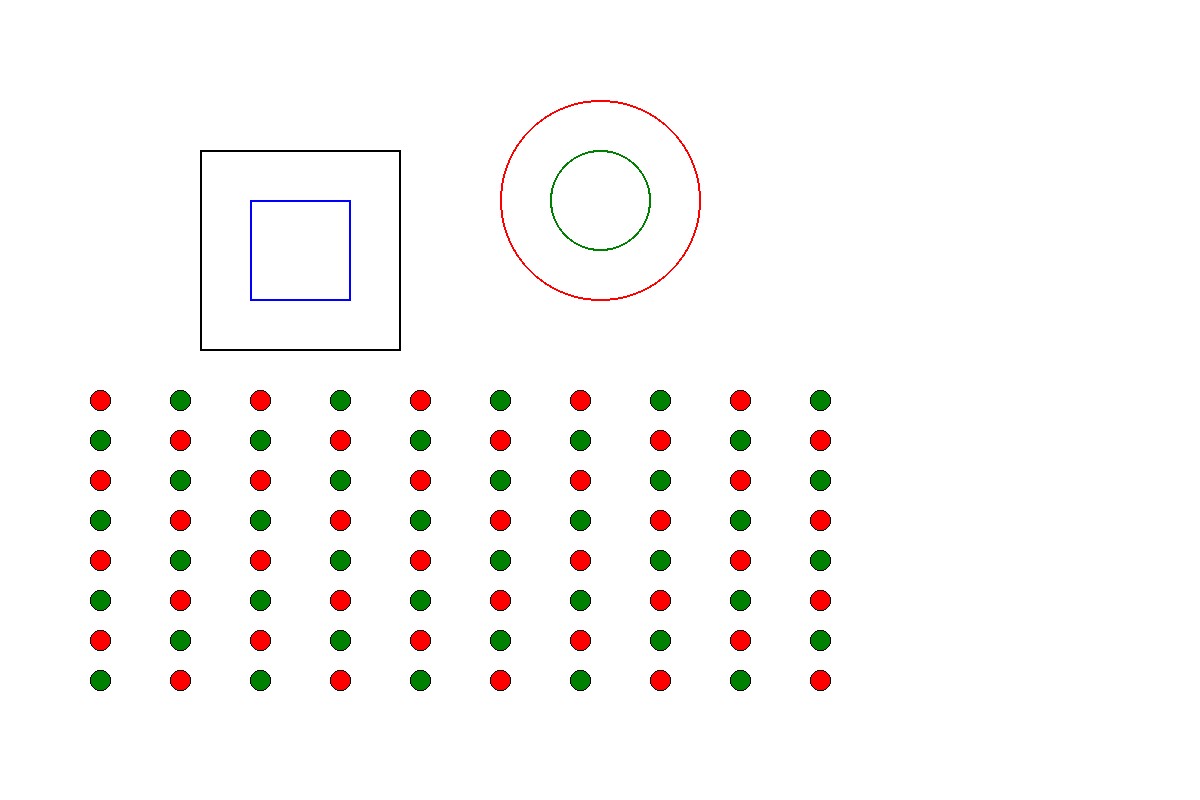

ตาบอดสี คืออะไร ตรวจได้ยังไง – คู่มือทั้งหมดปี

ตาบอดสี คืออะไร ตรวจได้ยังไง – คู่มือทั้งหมดปี 2026 ตาบ […]